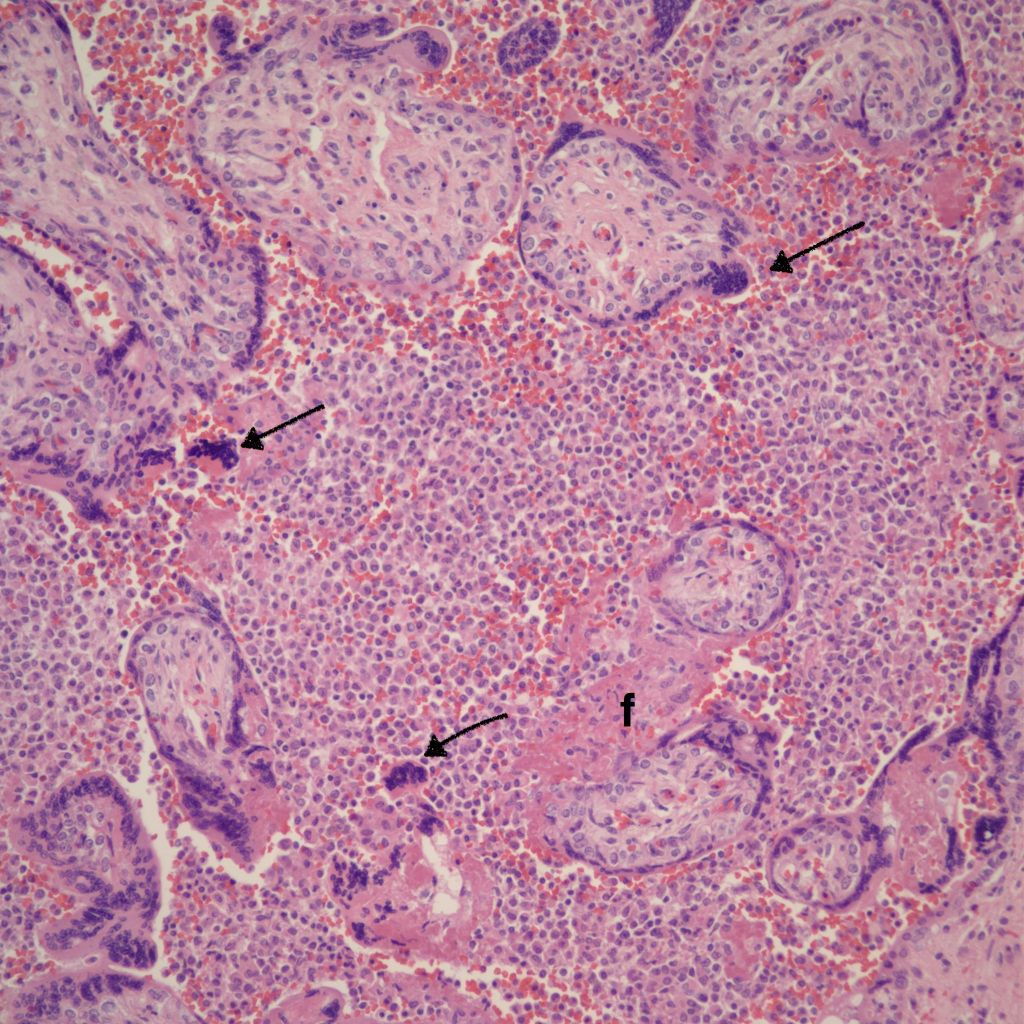

CHIV associated with Villitis of Uknown Etiology (VUE)

This pattern could be due to a primary cause of VUE with incidental chemotaxis of monocytes, two pathogenetically interrelated processes, or an incidental focus of VUE in a predominant CIIV disease. Currently, describing the extent of each process and its colocalization or lack of may prove useful until a better way to classify the co-existing lesions can be developed. One study has shown that there is a dichotomy between cases with c4d staining and those without c4d staining18.

Microscopic criteria: The primary criterion is monocytes clustered in the intervillous space which can be confirmed by CD 6810,17. The monocytes often have kidney bean shaped nuclei and prominent cytoplasm. Some other consensus criteria are that the inflammatory cells in the intervillous space should be at least 80% monocytes, and these should be maternal cells1,17.